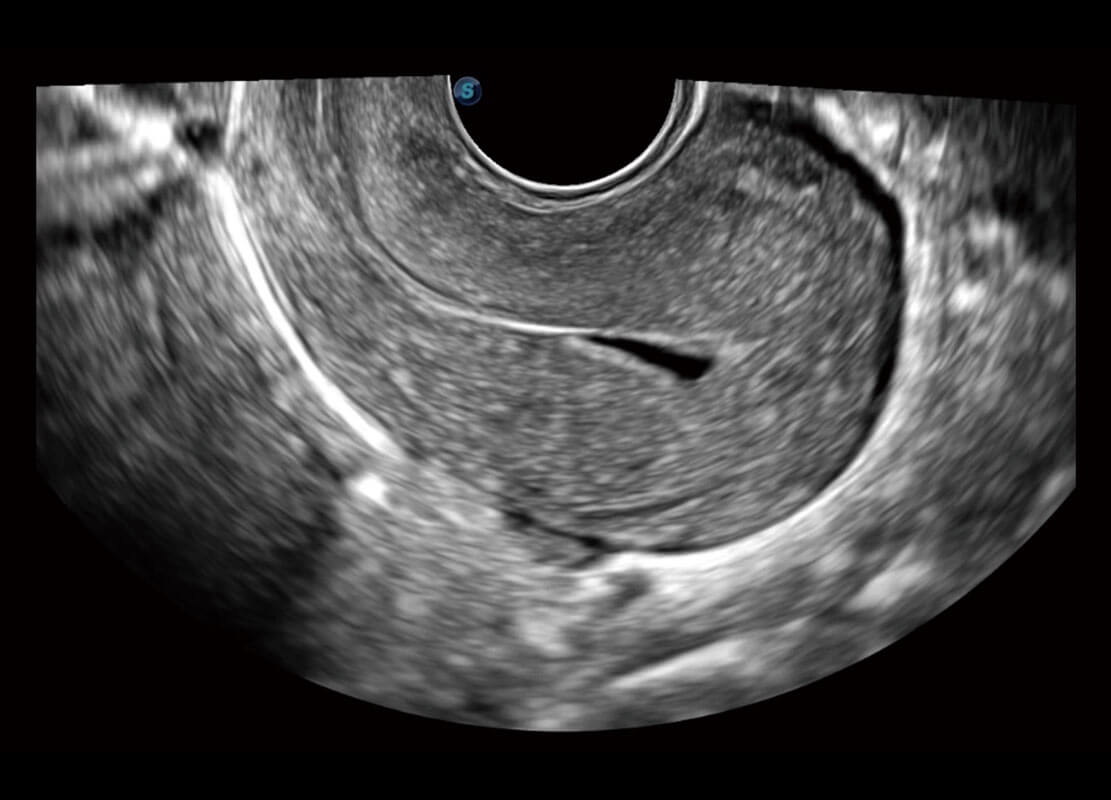

P60優(yōu)異的圖像質(zhì)量搭載專科探頭,在婦科基礎(chǔ)疾病的診斷、卵泡生長(zhǎng)的監(jiān)測(cè)、輸卵管通暢情況的判別等方面為您提供生殖應(yīng)用方案。

腔內(nèi)婦科-宮腔分離

腔內(nèi)婦科-卵巢